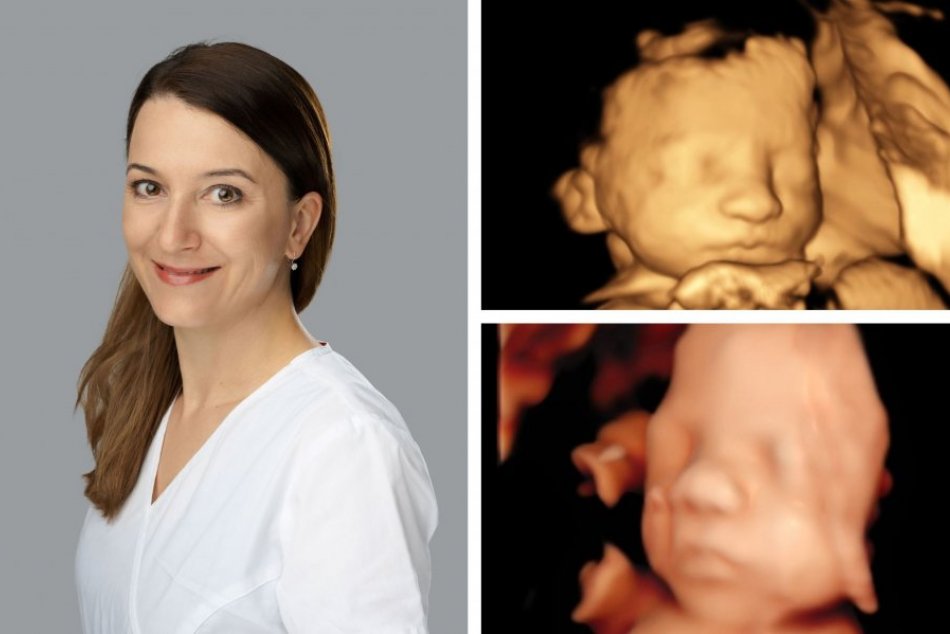

Nemocnica má pre budúce maminky ďalšiu novinku. Ženy, ktoré čakajú narodenie bábätka môžu absolvovať najmodernejšie skríningové vyšetrenie plodu v troj a štvordimenzionálneho obrazu.

"Software v ultrazvukovom prístroji je schopný vypočítať tretiu rovinu a my získame plastický obraz plodu. Štvrtou rovinou sa rozumie čas, tzn. dokážeme snímať videosekvenciu v plastickom obraze. Tieto techniky okrem toho, že budúca maminka odchádza s pekným obrázkom bábätka, napomáhajú aj v diagnostike vrodených vývojových chýb, napr. mozgu, chrbtice alebo aj srdca. Vo Zvolene pracujeme na vysokokvalitnom tzv. Highendovom prístroji a 3D/4D technológiou,“ vysvetľuje MUDr. Kristína Bihariová z gynekologicko-pôrodníckeho oddelenia Nemocnice AGEL Zvolen.

Pri 3D či 4D vyšetrení sa podľa Pavlikovejodhalí aj chybný vývoj vnútorných orgánov, najčastejšie sú to srdcové anomálie, ale aj vrodené chyby pľúc, obličiek, mozgu, alebo chýbanie resp. deformita končatín. „Detičky, ktoré nemajú v poriadku chromozomálnu výbavu, alebo majú iné metabolické ochorenie, mávajú súbor vrodených chýb na základe, ktorých sa dá predpokladať o aké základné ochorenie ide,“ hovorí MUDr. Bihariová.